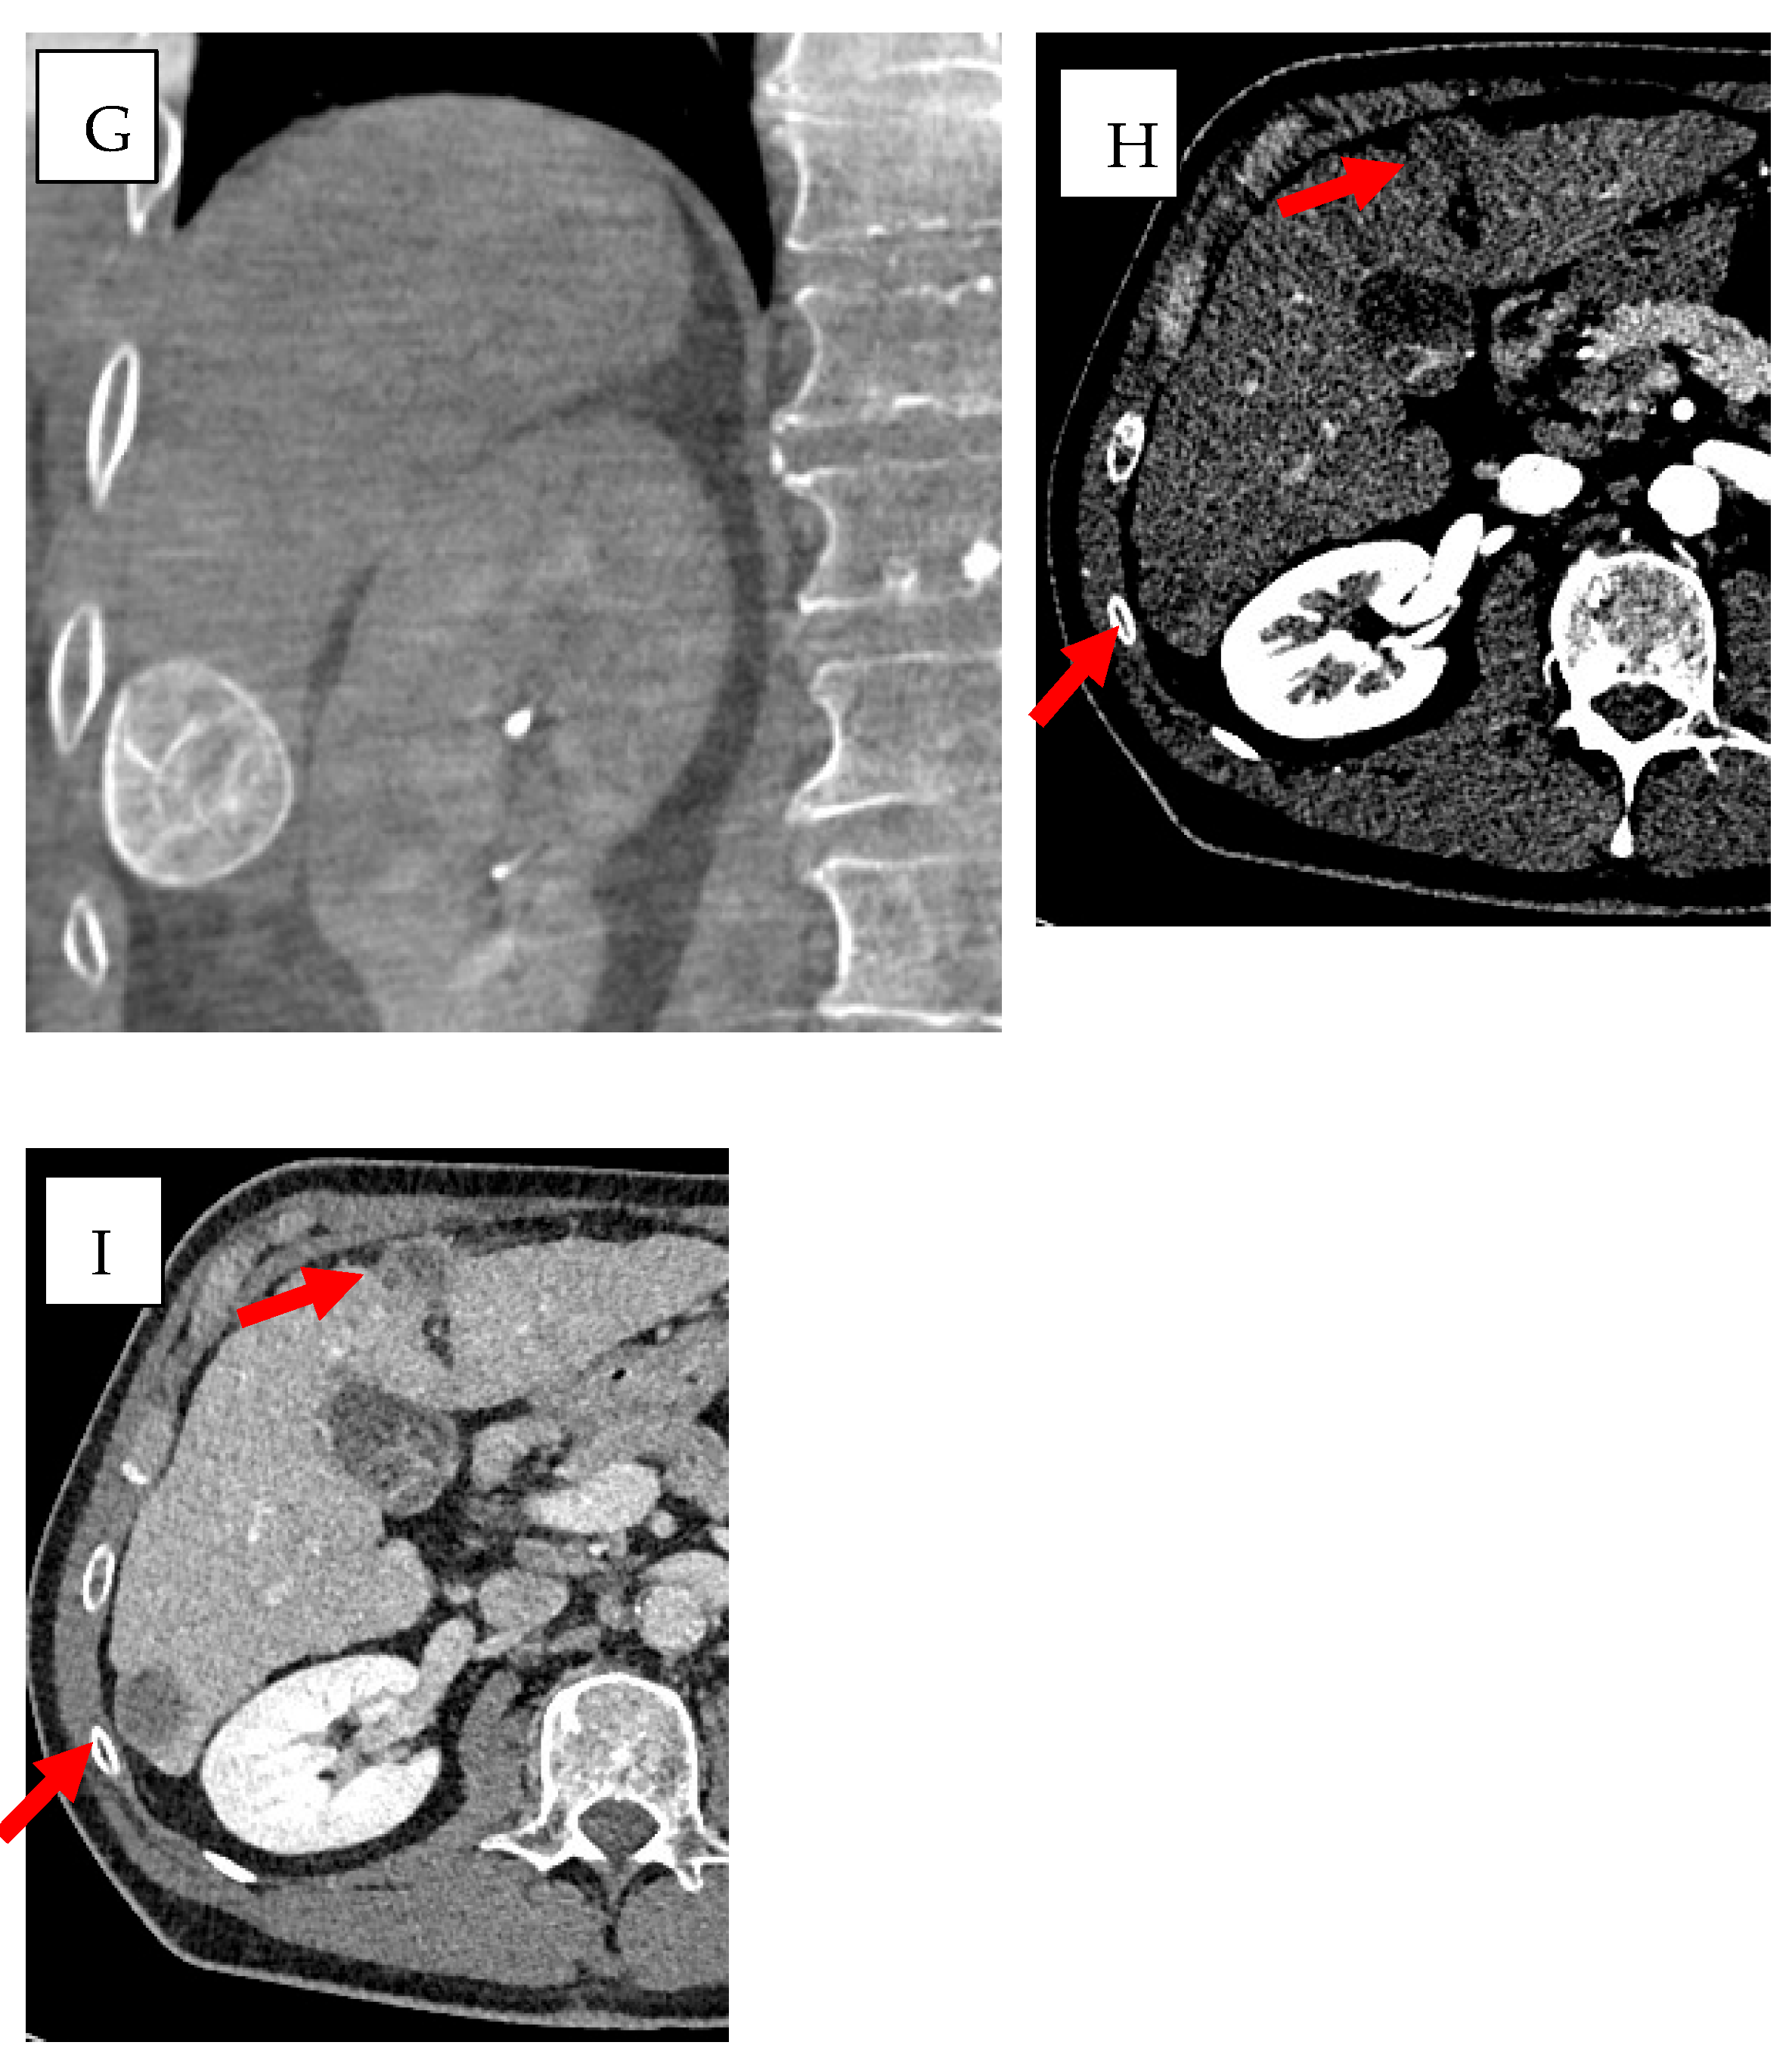

- Qin, S.; Liu, K.; Chen, Y.; Zhou, Y.; Zhao, W.; Yan, R.; Xin, P.; Zhu, Y.; Wang, H.; Lang, N. Prediction of pathological response and lymph node metastasis after neoadjuvant therapy in rectal cancer through tumor and mesorectal MRI radiomic features. Sci. Rep. 2024, 14, 21927. [Google Scholar] [CrossRef] [PubMed]

- Liu, C.; Zhao, W.; Xie, J.; Lin, H.; Hu, X.; Li, C.; Shang, Y.; Wang, Y.; Jiang, Y.; Ding, M.; et al. Development and validation of a radiomics-based nomogram for predicting a major pathological response to neoadjuvant immunochemotherapy for patients with potentially resectable non-small cell lung cancer. Front. Immunol. 2023, 14, 1115291. [Google Scholar] [CrossRef]

- Buijs, E.; Maggioni, E.; Mazziotta, F.; Lega, F.; Carrafiello, G. Clinical impact of AI in radiology department management: A systematic review. Radiol. Med. 2024, 129, 1656–1666. [Google Scholar] [CrossRef]

- Chehab, M.A.; Brinjikji, W.; Copelan, A.; Venkatesan, A.M. Navigational Tools for Interventional Radiology and Interventional Oncology Applications. Semin. Interv. Radiol. 2015, 32, 416–427. [Google Scholar] [CrossRef]

- Chehab, M.; Kouri, B.E.; Miller, M.J.; Venkatesan, A.M. Image Fusion Technology in Interventional Radiology. Tech. Vasc. Interv. Radiol. 2023, 26, 100915. [Google Scholar] [CrossRef]